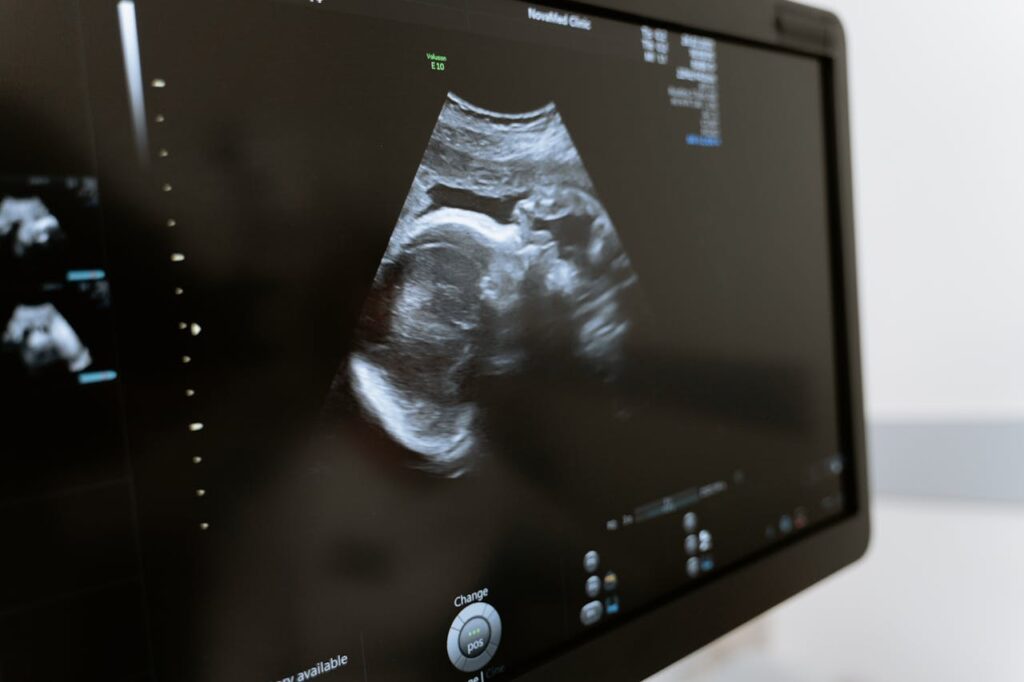

Las cardiopatías congénitas son las malformaciones que más se presentan los recién nacidos (en 1/125 neonatos, 0.8-1%). El 50% de las cardiopatías congénitas se consideran defectos mayores, presentan una mortalidad global del 25-35%, se asociación a otras malformaciones en un 20%, y a las cromosomopatías en un 20-40% por lo que presentan una alta mortalidad neonatal (25-35%). Por todo ello una evaluación adecuada en la ecografía morfológica es necesaria y fundamental y ante la presencia de una sospecha de patología o de la presencia de un marcador de posible cardiopatía se debe realizar lo que se llama una ecocardiografía morfológica y funcional fetal

En nuestro servicio esta exploración se realiza con ecógrafos de gama alta y por personal especializado en este tipo de ecografía, con la finalidad de obtener un diagnostico prenatal acertado que nos facilite un asesoramiento de este tipo de patología fetal.